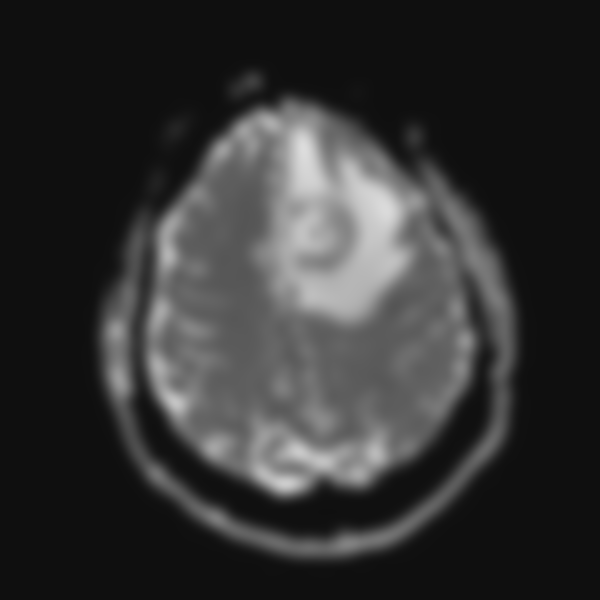

46.49歲男性平常有高血壓,因突發性右側肢體無力及麻木而就診,就診當天的無顯影劑腦部電腦斷層(non- contrast CT)檢查結果如下圖①,5天後的腦部磁振造影(MRI)檢查結果如下圖②(Fluid attenuated inversion recovery, FLAIR)及圖③無施打顯影劑之T1影像。下列何者最有可能是此病人的診斷?